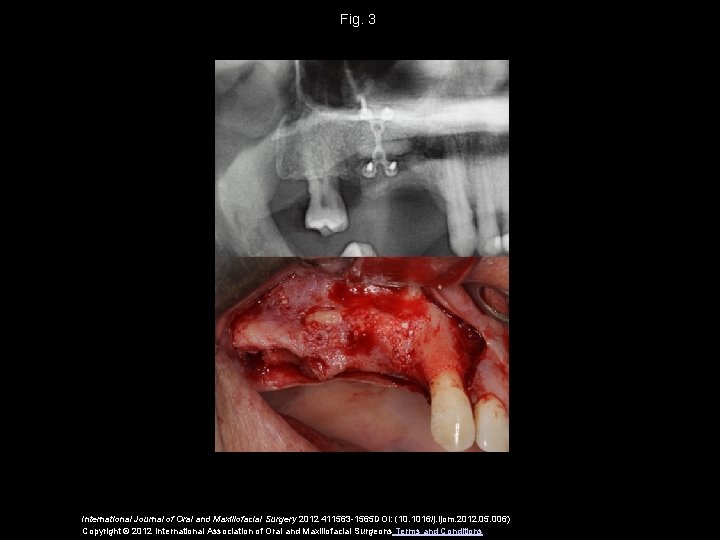

Fig. 3 International Journal of Oral and Maxillofacial Surgery 2012 411563 -1565 DOI: (10. 1016/j. ijom. 2012. 05. 006) Copyright © 2012 International Association of Oral and Maxillofacial Surgeons Terms and Conditions